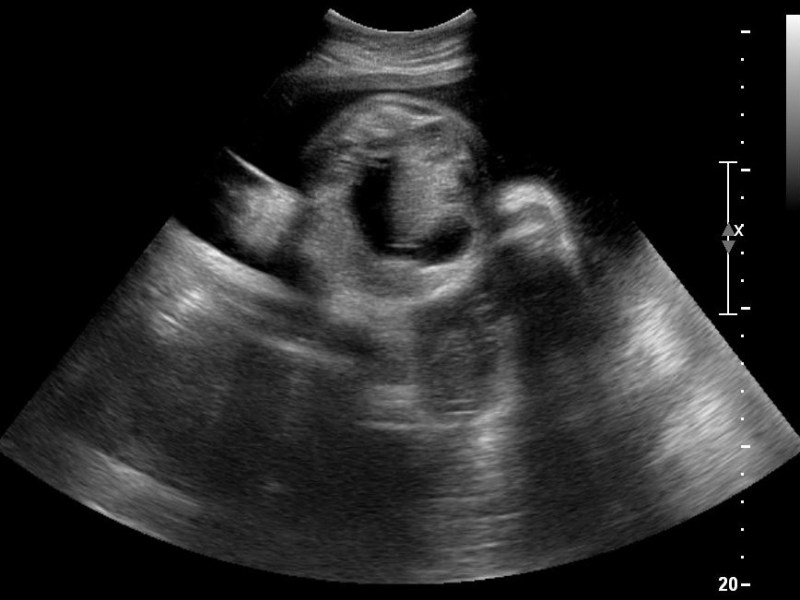

- Magnification of the image including only the fetal head and upper thorax.

- Medial view of the fetal face in a true sagittal section of the fetus, defined by the presence of the echogenic tip of the nose and rectangular shape of the palate anteriorly, the translucent diencephalon in the center and the nuchal membrane posteriorly.

- Calipers should be placed on-on to measure NT as the maximum distance between the nuchal membrane and the edge of the soft tissue overlying the cervical spine.